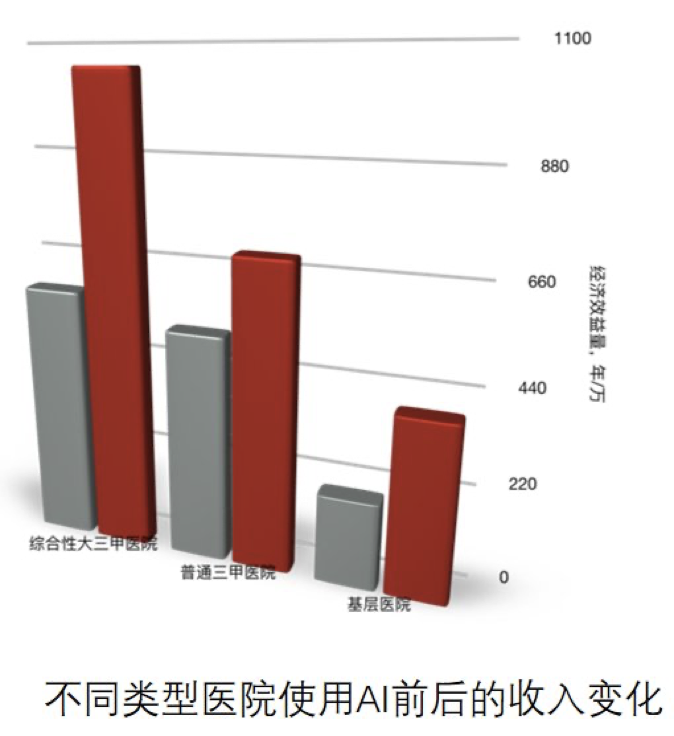

另一方面,医院的成本降低、收入增加。之前医院可能需要 10 台或者 20 台工作站,并且每台都比较贵,可能需要 20-30 万,现在可以替换为一台中央服务器,以私有云的方式在医院部署起来,运行我们的 AI 产品,使用算法的服务,每个医生用一台普通电脑只需要几千块钱的成本连到服务器,就可以完成跟之前一样的事情,医生的工作时间减少,工作质量上升,医院的收入增加。右边的图是一个对比,即不同类型三甲医院、基层医院在使用冠脉 CTA 产品前后收入的变化,收入有显著的上升,因为诊断的病人增多了。